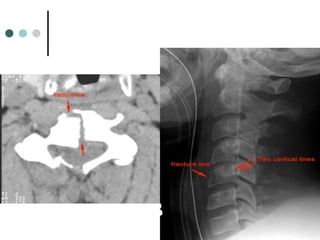

JEFFERSON FRACTURE

 Compression fracture of the

bony ring of C1, characterized

by lateral masses splitting and

transverse ligament tear

 Mechanism: Diving into shallow

water, RTA

 Best seen on Odontoid view

 Signs: Displacement of the

lateral masses of vertebrae C1

beyond the margins of the body

of vertebra C2

 Radiographic features:

the key radiographic view is the AP open mouth, which shows

displacement of the lateral masses of vertebrae C1 beyond the

margins of the body of vertebra C2. A lateral displacement of >2

mm or unilateral displacement may be indicative of a C1

fracture. CT is required to define the extent of fracture and to

detect fragments in the spinal canal.

Stability: unstable

 the lateral displacement of C1

indicates a Jefferson fracture.

odontoid view, which illustrates the lateral

displacement of C1